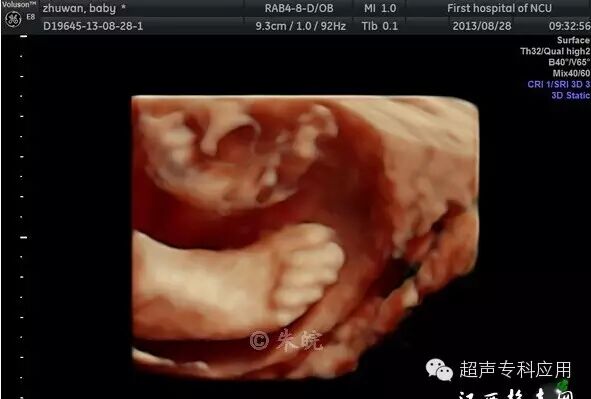

1.1 表面结构的成像 这是三维超声最初在胎儿显像的应用。早孕期可显示整个胎儿的形态以及头颅、腹壁、四肢等;中孕期则能显示胎儿头面部、手指(脚趾)等相对细小的结构。这些表面结构的三维图像,客观逼真,一旦存在胎儿体表的畸形,如唇裂、脑膨出、脊柱裂、脐膨出、腹裂、肢体或手脚畸形,三维成像能够让孕妇及家属一目了然,让产科医生或儿科医生更结合实际情况进行咨询,方便选择下一步的处理方案。虽然三维超声对体表畸形的诊断可能并不比二维超声提供更多信息,这些体表畸形可能在二维声像图上也较容易显示,但孕妇及家属却不理解二维图像,难以想象畸形外观如何、有多严重。为了更人性化的服务,目前,也有不少医院或产院对孕妇提供“胎儿照相”;四维超声观看胎儿运动并录像,以留作纪念。三维表面成像的重要条件是感兴趣区域前方一定要有足够的羊水,而且不能被肢体、脐带等遮挡。羊水过少或晚孕期胎儿充满官腔时,三维表面成像则有较大困难。

胎儿唇裂表面三维成像